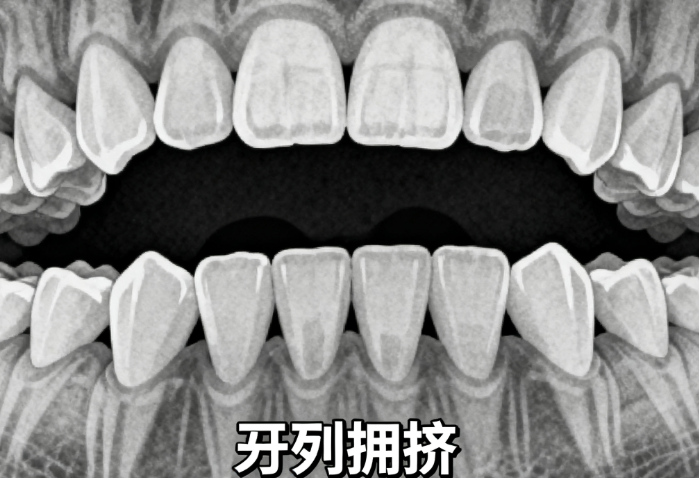

6-12岁是孩子牙齿发育的关键阶段,不少家长开始关注“6-12岁跑牙齿矫正器”是否适合孩子。这个年龄段的孩子正处于替牙期,牙齿和颌骨都在快速发育,一些常见的牙齿问题如牙列拥挤、地包天、牙弓狭窄等,若不及时干预,可能会对恒牙期造成更复杂的影响。近年来,随着儿童口腔健康意识的提高,越来越多的家长开始考虑为孩子使用牙齿矫正器。但“6-12岁跑牙齿矫正器”是否真的适合每个孩子?需要结合孩子的具体问题、医生建议以及家庭配合情况综合判断。

医生通常建议,如果孩子存在牙弓狭窄、地包天、牙列拥挤等骨骼或牙齿问题,可以考虑使用牙齿矫正器进行早期干预,以引导颌骨和牙齿的正常发育。

ETA早期干预矫正器适用于替牙期牙列拥挤、前牙反颌等情况,通过扩弓装置改善牙弓宽度。